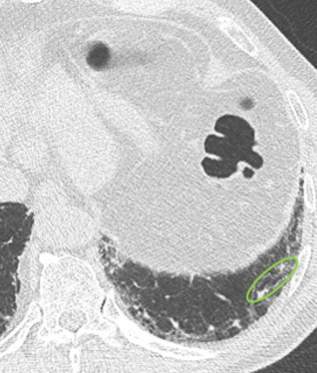

Der behandelnde Arzt hat sich für eine hochauflösende Computertomographie

(HRCT) des Thorax entschieden und folgende klinische Befundung erhoben:

Befundung des HRCT-Scans:

- Retikuläre Veränderungen

- Milchglasartige Dichteanhebungen

- Traktionsbronchiektasen

- Nicht vorhanden: Honigwabenmuster

CT: Computertomographie | HRCT: hochauflösende Computertomographie

10 Monate nach dem ersten Scan

CT bei der Erstpräsentation